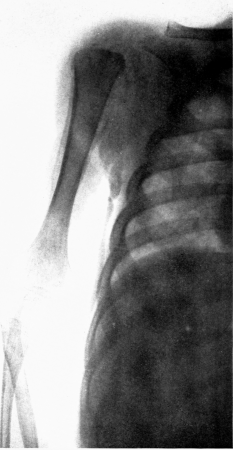

| 6. | Subperiosteal hemorrhage and separation of epiphysis. Roentgenogram | 109 |

| 7. | Complete restitution of epiphysis without deformity. Roentgenogram | 109 |

| 16. | Subperiosteal hemorrhage and separation of epiphysis. Roentgenogram | 192 |

| 17. | Periosteal “tags” and “streamers.” Roentgenogram | 193 |